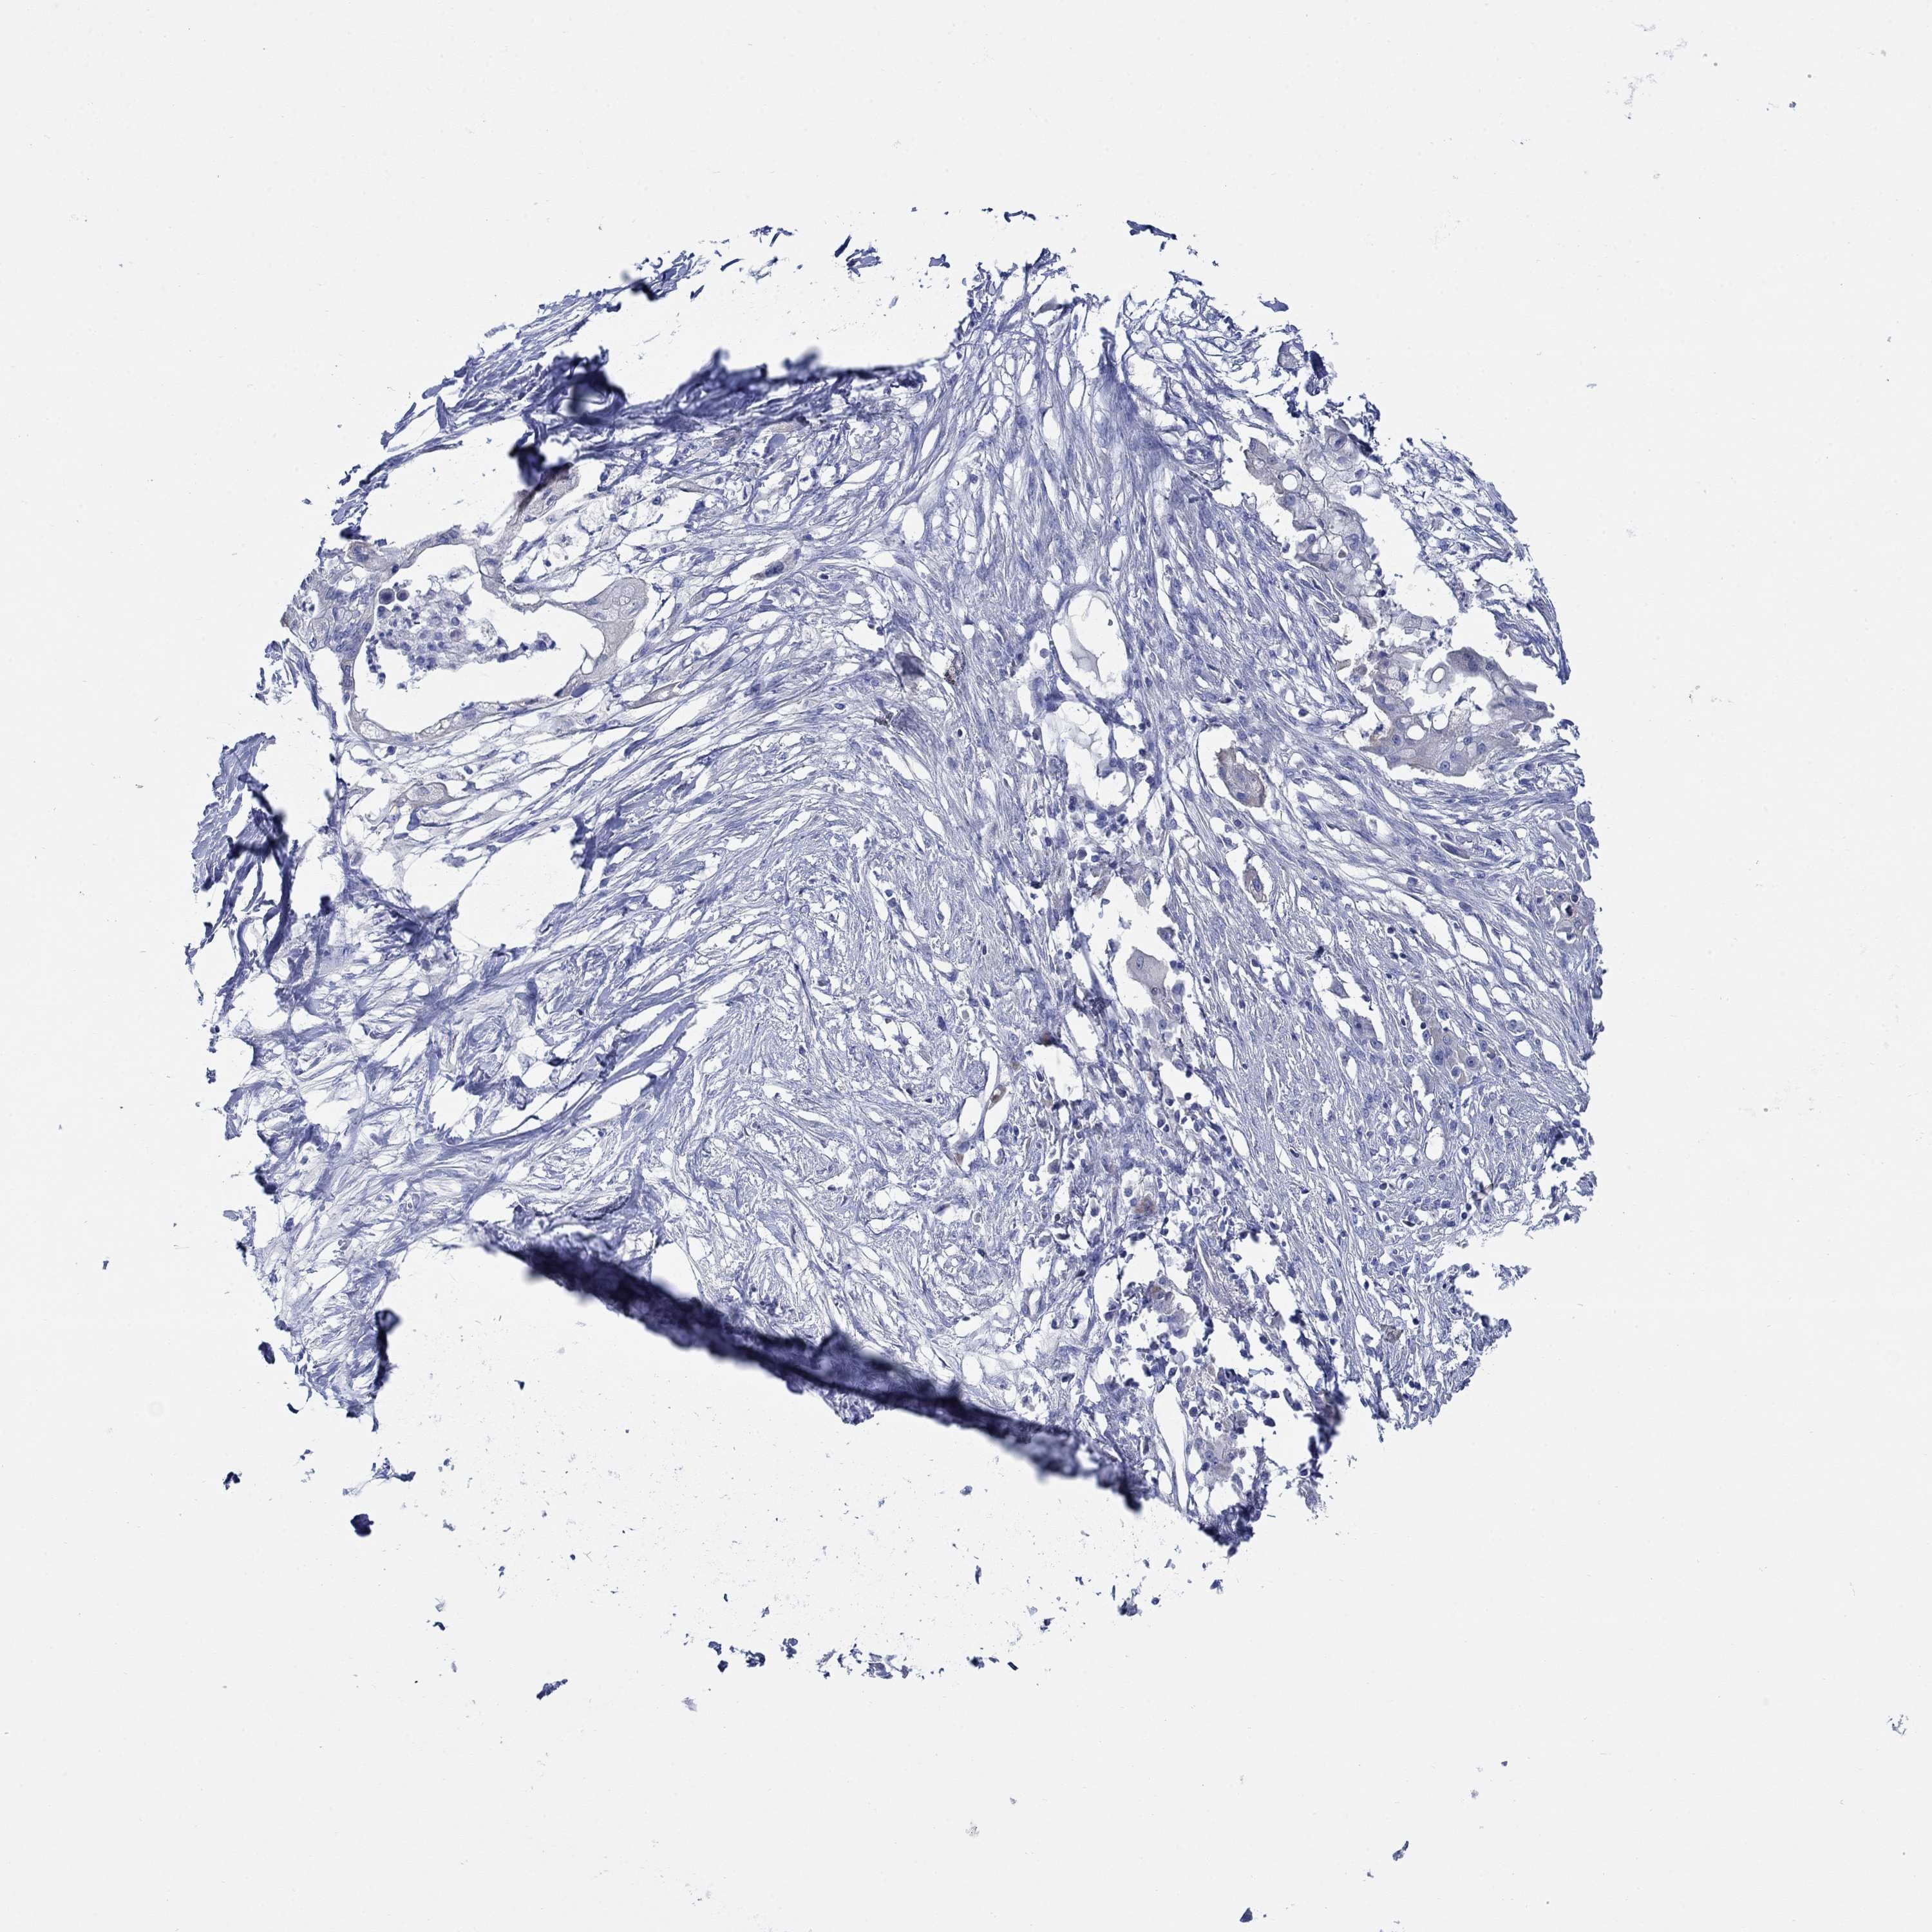

PANCREATIC CANCER - Protein expressioni

A mouse-over function shows sample information and annotation data. Click on an image to view it in a full screen mode. Samples can be filtered based on level of antibody staining by selecting one or several of the following categories: high, medium, low and not detected. The assay and annotation is described here.

Note that samples used for immunohistochemistry by the Human Protein Atlas do not correspond to samples in the TCGA dataset.

Antibody stainingi

Antibody staining in the annotated cell types in the current human tissue is reported as not detected, low, medium, or high, based on conventional immunohistochemistry profiling in selected tissues. This score is based on the combination of the staining intensity and fraction of stained cells.

Each image is clickable and will lead to virtual microscopy that enables deeper exploration of all samples and also displays staining intensity scores, fraction scores and subcellular localization as well as patient and tissue information for each sample.

Antibody HPA023623

Antibody HPA066431

Adenocarcinoma, NOS